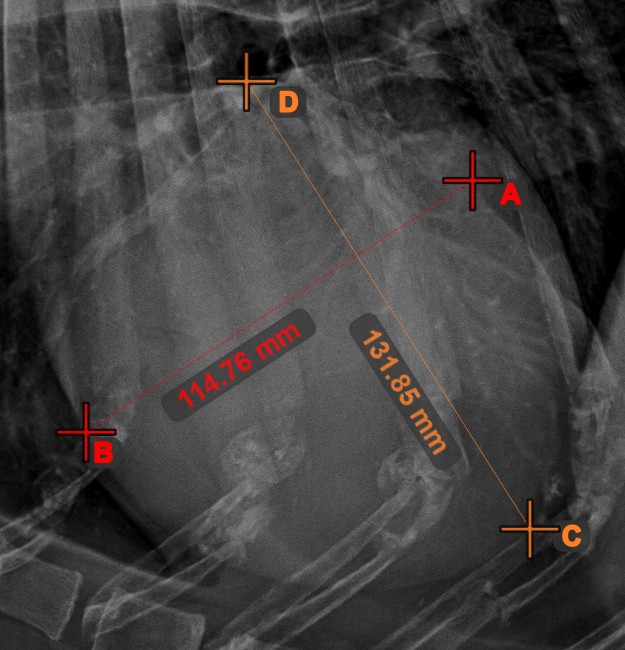

Vonalak metszéspontja¶

Gyorsan és pontosan találja meg és jelölje két meglévő vonal közti metszéspontot a Vonalak metszéspontja eszközzel.

Válassza ki az eszközt a bal oldali eszköztárból, és rendelje hozzá az egyik elérhető egérgombhoz. Válasszon ki két, a jelenetben már meglévő vonalat a mérés elvégzéséhez. A vonalak metszéspontja automatikusan kiszámításra kerül és jelölésre kerül a jelenetben. Két vonal metszéspontját mindig az X betű jelzi.

Információ

Ha két vonal közvetlenül nem metszi egymást, a jeleneten azok meghosszabbított vetületeinek metszéspontja lesz jelölve.